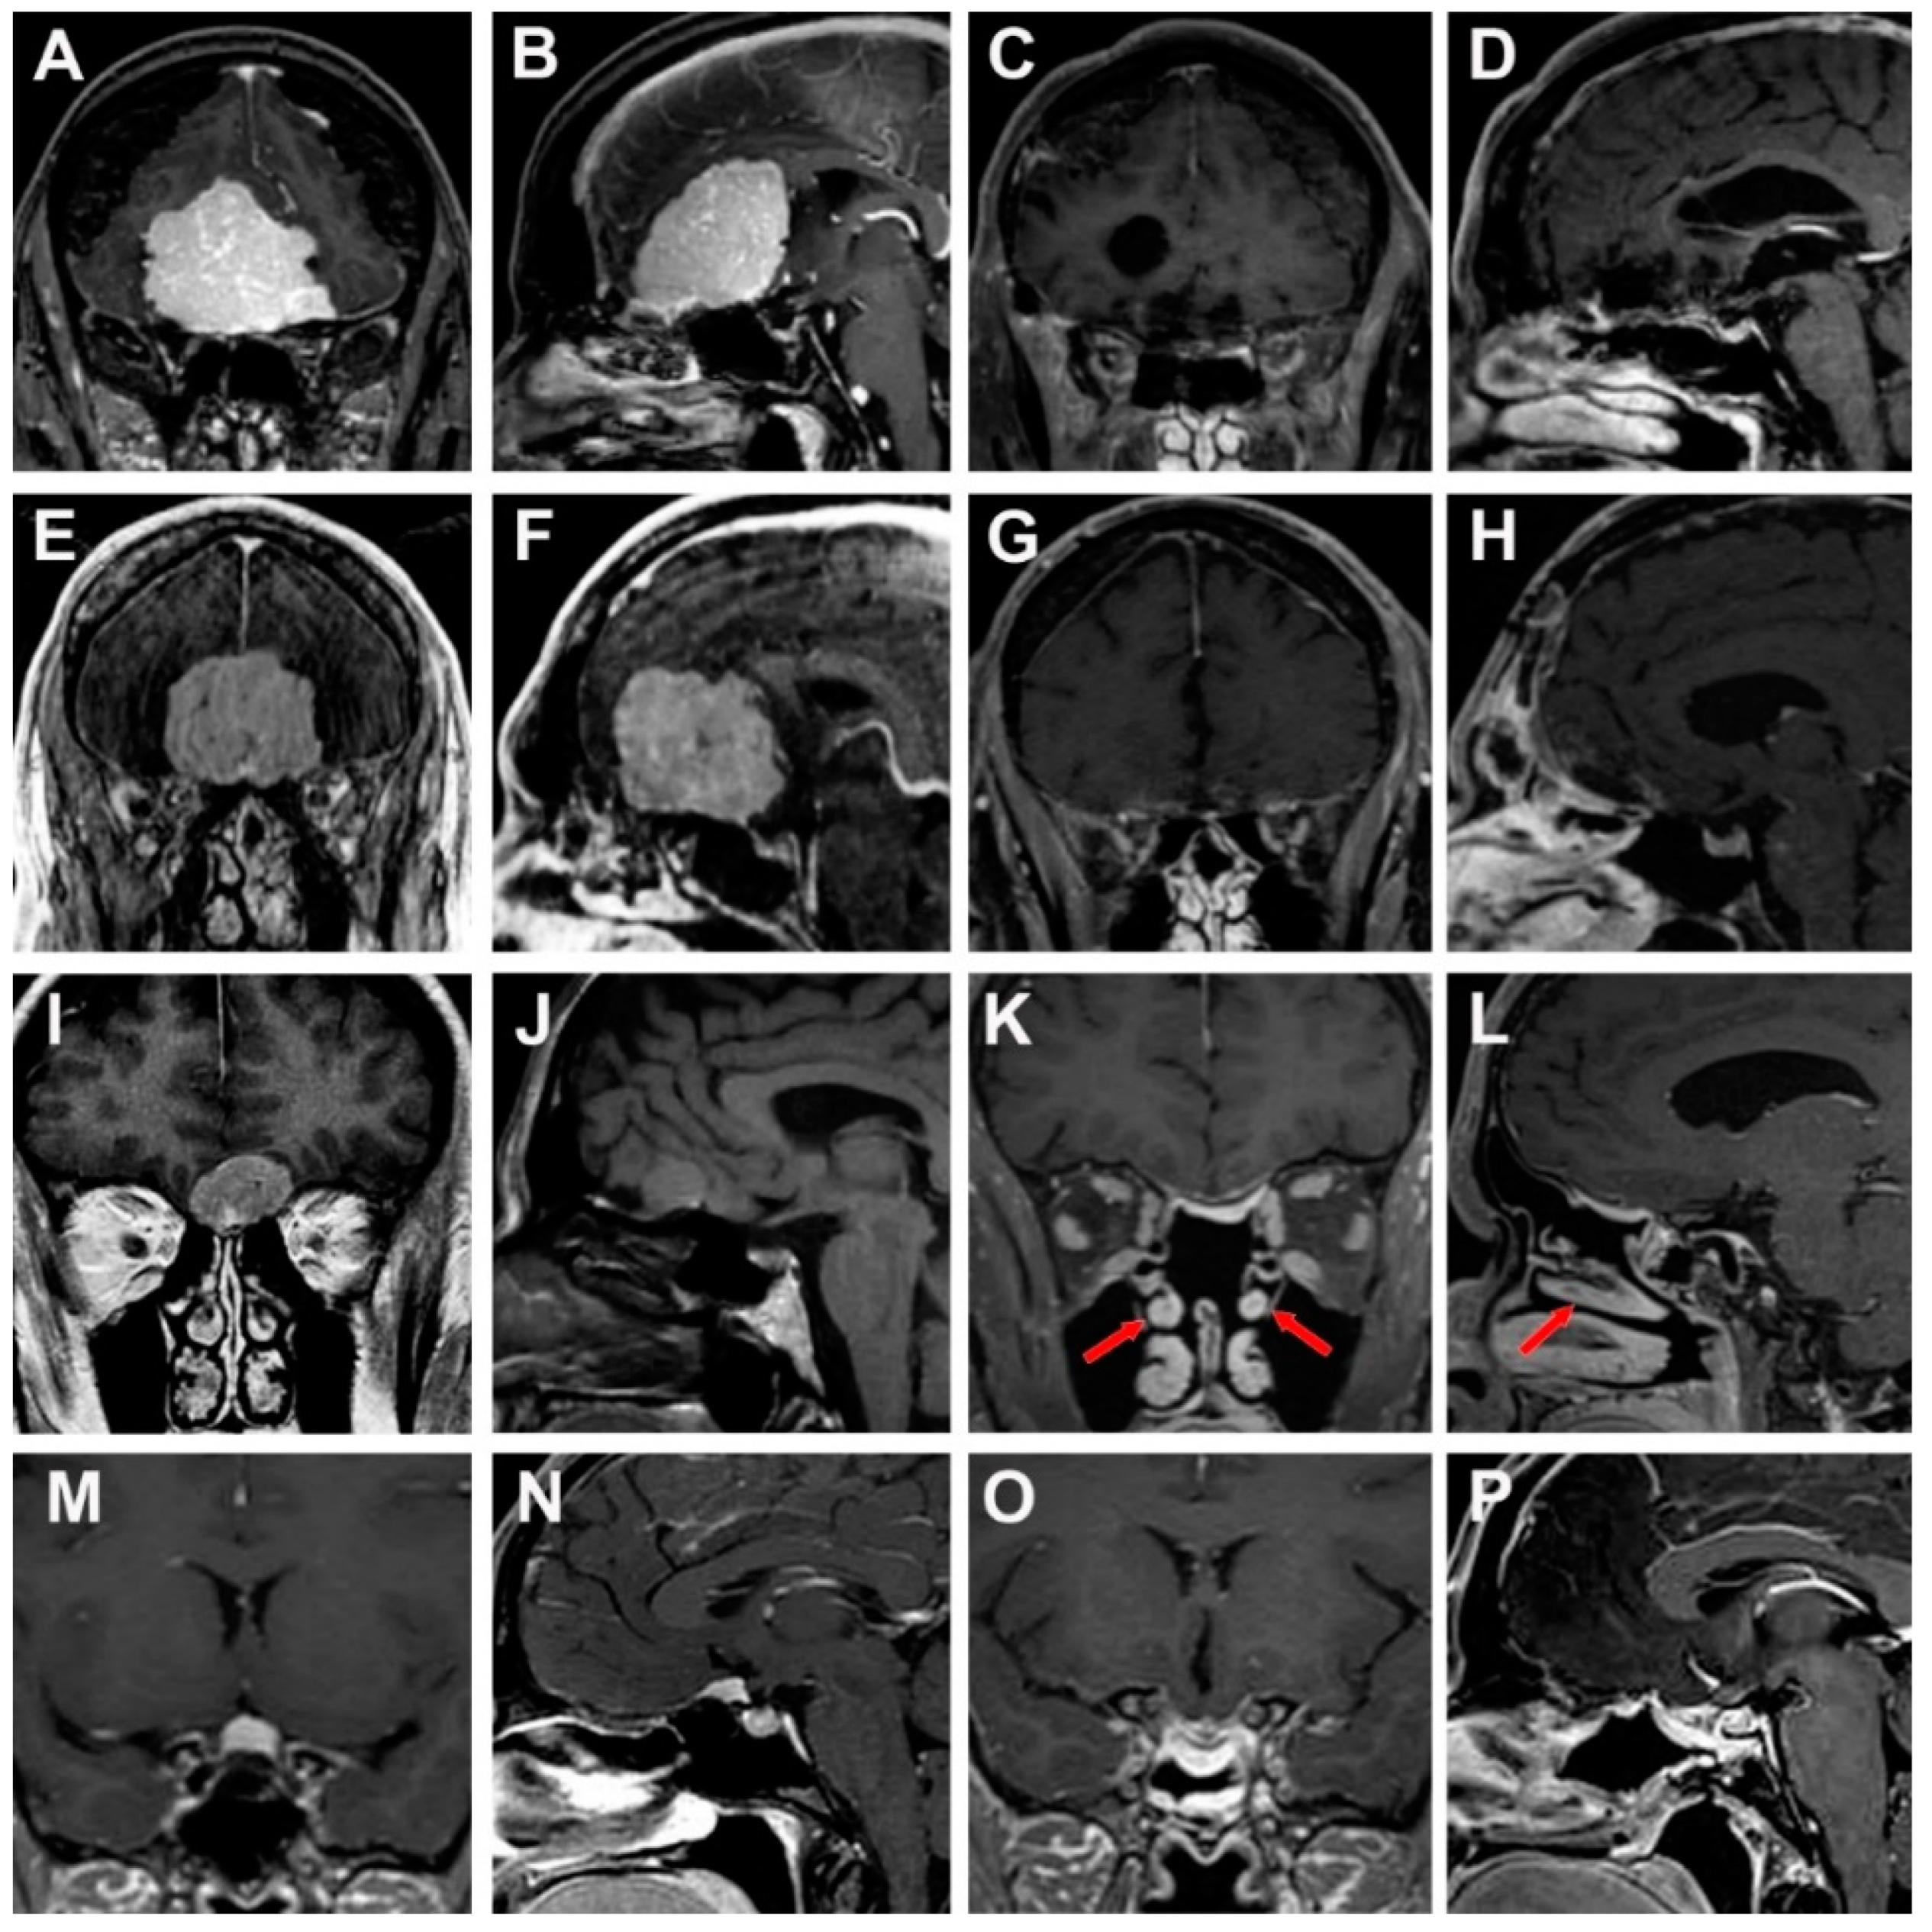

3.4. Illustrative Cases

3.4.1. Case 1

3.4.2. Case 2

3.4.3. Case 3

3.4.4. Case 4